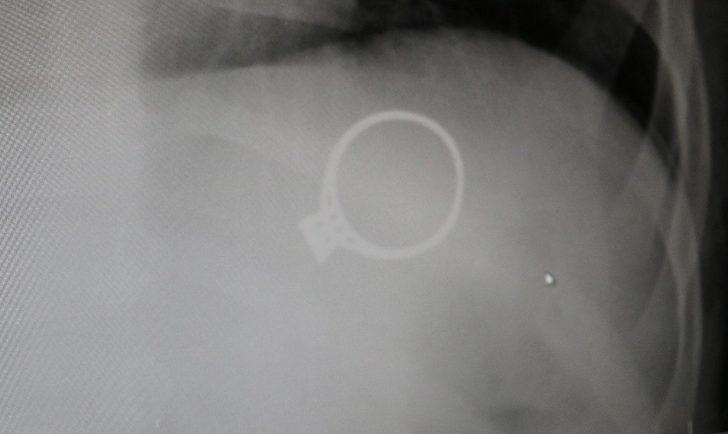

Sivas’ta kent merkezinde yaşayan F.G. ve C.G. çiftinin 1.5 yaşlarındaki M.G adındaki bebekleri oynamak için annesinden tek taş yüzüğünü istedi. Yüzükle oynayan M.G. annesine fark ettirmeden yüzüğü yuttu. Bir süre sonra çocuğunun yüzüğü yuttuğunu fark eden anne çocuğunu kucaklayarak Sivas Medicana Hastanesine götürdü. Burada Çocuk Cerrahisi Uzmanı Op.Dr. Mahmut Aluç tarafından muayene edildi. Yüzüğün, röntgeni çekilen M.G’nin midesinde olduğu görüldü. 6 gün sonra yüzük doğal yollarla çıktı. Çıkan yüzük aileye rahat bir nefes aldırdı.

RÖNTGENDE BELLİ OLDU

Çocuk Cerrahisi Uzmanı Op.Dr. Mahmut Aluç, çekilen röntgende yüzüğün midede olduğunu belirlediklerini ifade ederek, “Hastamız 1 buçuk yaşında. Bundan 6 gün önce bize yüzük yutma şikayeti ile başvurdu. İlk çektiğimiz grafide yüzüğün mide de olduğunu saptadık ve aileyi bilgilendirdikten sonra rutin prosedürlerinin gereği beklemeye başladık. 6 gün sonra spontane olarak yüzüğün kendisi çıktı. Bu tür hastalarla oldukça sık karşılaşıyoruz. Rutin olarak şöyle bir kural vardır, çocuk ağzına aldığı her şeyi yutabilir. Özellikle küçük çocuklar cisimleri tanımak için elleriyle dokunduktan sonra genellikle ağızlarına alırlar. Bu yutulan cisimler toplu iğne olabilir, çengelli iğne olabilir, para olabilir” dedi.